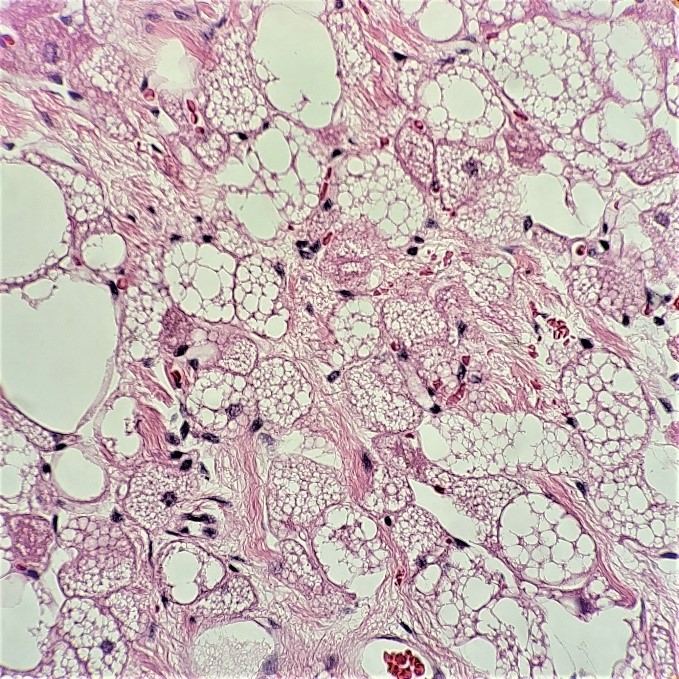

What non-heme surprise is THIS?! Are these histiocytes? There’s no way, those nucleoli are aggressive! Look at the chromocenters! The variation in nuclear size! What epithelial beauty is this? Is it epithelial?! Is that a fibrovascular core? It can’t be sarcomatoid, could it? Twenty inner monologue questions later, “okay, it’s adequate,” I said to the radiologist. But wait… should I do it? Should I press for a core biopsy? The radiologist asked me if I needed anything else for the diagnosis. Perhaps she saw my puzzled expression, compelling her to tell me that she felt the imaging looked weird – she thought it wasn’t a heme case either. At least I’m not alone here. I took a deep breath, expecting the worst and hoping for the best, and I asked the radiologist to collect a core biopsy. She checked the ultrasound Doppler for excessive vascularity, and much to my surprise, she agreed to perform the core. After collecting more FNAs for my cell block and dropping the core biopsies off in surgical pathology, I showed the case to my attending pathologist. He also agreed that we don’t need to triage it for heme. He asked if the patient had any significant history other than PV, splenic lesions, and brain mets, and I told him nothing was reported in his chart. I checked the chart again for good measure while he was running through his differential diagnoses of lung, GI, prostate, etc., and saw the patient was scheduled to see dermatology later that week. I mentioned to that to my attending, and he suggested it could be a melanoma.

The following morning, I examined the pap-stained slide and began to second guess myself. Was I wrong? Could it be a heme case? Hodgkin’s wasn’t in the differential, and these cells look so much more aggressive than Reed-Sternberg cells. At least we have a core biopsy either way. We could run immunos on the cell block and save the cores for molecular. I screened the pap-stained slides a little longer, focusing on the macronucleoli, the owl-eye and eccentric nuclei, the poorly-differentiated nature of this… MELANOMA. YES! So, the cells might not contain any melanin pigment, but my attending’s inkling was exactly right. Waiting for my cell block to arrive, I listed melanoma as my primary diagnosis with a differential of lung or prostate cancer.

The cell block confirmed my non-heme diagnosis and kept my differentials at bay. The attending pathologist ordered an immunohistochemistry profile of S100, HMB-45, and Melan A, as well as AE1/AE3. The first three immunostains (prior to our adoption of SOX-10) confirmed a diagnosis of metastatic malignant melanoma. Soon thereafter, the patient’s primary lesion was identified on his back, and he was treated with radiation and immunotherapy. Unfortunately, the metastases were not responding to the immunotherapy, and a few days after a clinical trial was offered, the patient passed away.

Melanoma is known as the great mimicker, especially in amelanotic form, and it should always be in the back of your mind as a differential diagnosis. Lack of melanin pigment and a large cherry red macronucleoli leads us to favor lung, prostate, or serous adenocarcinoma), renal cell carcinoma, hepatocellular carcinoma, Hodgkin’s lymphoma, or even an epithelioid sarcoma. This case highlights the need to remember that metastatic melanoma is always a possibility, even when you do not have a primary site or previous clinical history of the disease.